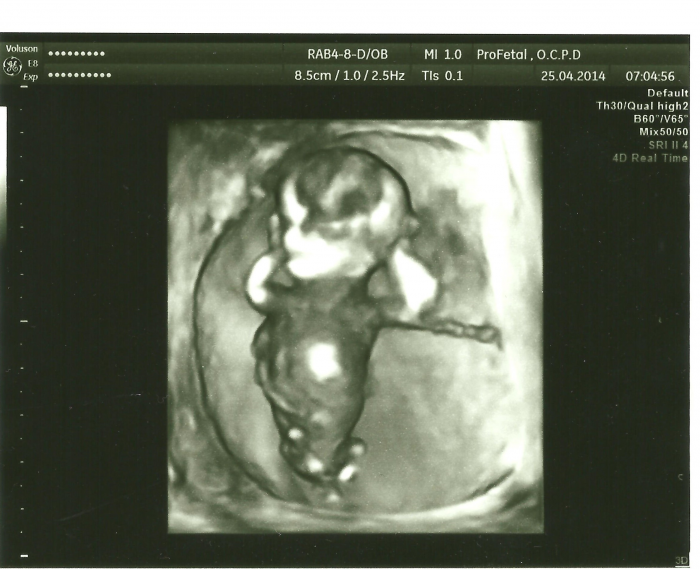

No tak to je divný teda. Jestli ti na tom prvním screen vyšlo vše ok. Tak ty tripple testy jsou podle mě zbytečný. A mě to mozek nebere teda. Já mám právě dokument z toho prvního screen a mám tam popsáno vše. I kolik má tepů za minutu a močový mechyr a páteř atd. Všechno mi to projela. A udělala mi zápis jako blázen. Poučila mě a vysvětlila rizika. Mám tam i nějaké populační rizika (což úplně přesně nechápu ) a potom tam mám upravené riziko z mojich výsledků. a to riziko mám nízké ,řeklj bych že i docela dost nízké. Třeba na toho downna . Ale stejně si porad říkám ,že stát se může cokoliv. a porad si v hlavě říkám ať je to v pořádku. Jestli můžu doporučit doktorku tak je to mudr. Frisova . Všechno vysvětlí a fakt se vám věnuje.

Ja v tom svym papiru prave nic moc nemam.zaver ale napsali, ze plod je bez zjevnych vyvojovych vad.jsem fakt zvedava, co mi v pondeli reknou.ale 14000 uz si pripravujem.s nejistotou bych to asi do porodu nevydrzela.

naposledy jsem tu byla před pěti týdny, to jsem byla 13 tt a pak jsem si přestala těhotenství užívat, protože 1 screning mi vyšli špatně výsledky - riziko 1:110 na Downuv syndrom. takže pohovor u genetika, ten mě poslal na odběr placenty, takže jsem jela do Ostravy na odběr, který se nakonec nekonal z toho důvodu, že by se doktor nedostal k placentě, protože ji mám umístěnou vzadu a hned mi tam přepočítali že mám ještě větší riziko 1:85. Takže jsem jela zase domů totálně na dně s tím že za dva týdny jdu zase a to na odběr plodovky. O odběru jsem vůbec nepřemýšlela jestli jít nebo ne, prostě jsem chtěla vědět zda bude dítě zdravé. Víc mě vadilo že bych po odběru musela cestovat 2 hodiny busem, takže mi moje doktorka přeobědnala odběr do Havířova,kam jsem ráno přijela, sestřička udělala papíry a zjistila jsem že už amniocentézu nedělali rok a půl. Jenže pan Doktor Janíček byl tak opatrný a hodný že jsem absolutně nic necítila, vůbec to nebolelo a ještě si mě tam nechali pro jistotu ležet do 11 hodin. bylo to rozhodně lepší než v Ostravě kde berou všechny jak na běžícím páse a hned tě posílají domů. Pak jsem dodržela 2 dny klid, fakt jen ležet a na záchod a zase ležet. No a nastalo čekání na výsledky, 2 týdny ve stresu, nervy v kýblu. Dnes jsem 18tt volala jsem na výsledky a naštěstí to bude zdravá holčička <3 Jsem ten nejšťastnější člověk na světě. dneska jsme si s přítelem pobrečeli, úplně se nám ulevilo a začínáme si užívat těhotenství.

Ahoj holky,tak jsem vcera byla na tom ultr.ohledne rozstepu patere a vse bylo ok,az na to,ze kdyz jsem se oblekala,doktor rekl at si jeste lehnu,ze mu tam neco nesedi.znova premeril steheni kostia rekl ze jsou mebsi nez by meli byt a ze to byva u Dawna!pritom v 1.trilestru me vysel Dawn 1:100000 takze ok,sam se divil a ted tohle.hned me rekl ze doporucuje idber plodovku,to udelal rovnou,nebala jsem se ale to bodnuti dost prekvapi tak sem jeste stala svali a to bylo neco.ale da se to vydrzet.ted druhy den lezim,musela jsem dnes jeste na hodku do prace mam to pres silnici,tak doufam ze se nic nesrane.clovek jde s podezrenim na rozstep a odchazi s Dawnem!Ja to nechapu....Hlavne me desi kdyby to bylo s krve tak strach nemam ale kdyz to vudel na ultr.tak mam fakt strach.Dnes ve dve uz budou vysledky,zatim jen na Dawna.Holky co vas to ceka drzim pesticky!